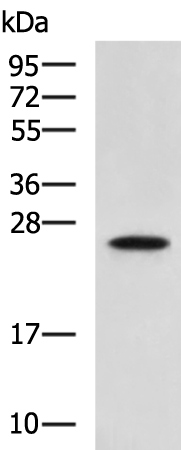

分类: 科研抗体货号: P02794别名:应用: WB,IHC反应种属: Human, Mouse, Rat